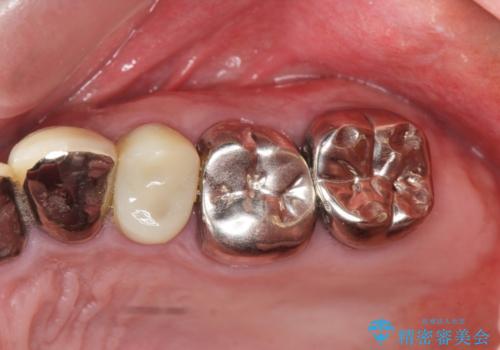

虫歯だらけの歯を治療したい

- 「虫歯が多発し、治療が終わらない。歯も無くなったし今後悪くならないような治療をしたい。」と精密治療を希望され来院されました。

虫歯の徹底的な除去やセラミック補綴、精密根管治療、歯周外科を行うことで、治療後に歯磨きがしやすく、かみやすい機能的な仕上がりへと導きます。